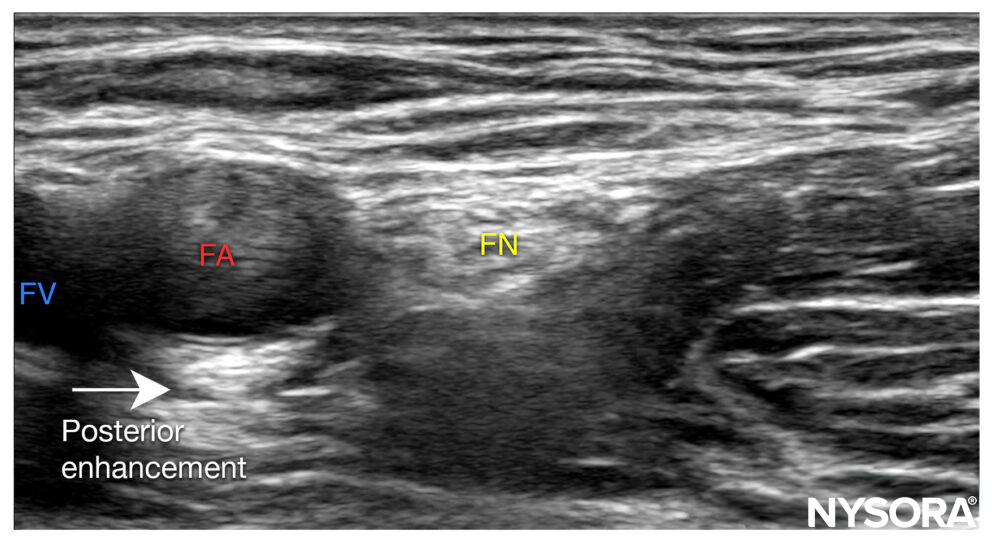

Enhancement

Sound waves travel faster in structures with low acoustic impedance, resulting in brighter areas directly below these structures (e.g., bladder, vessels). Enhancement can make it harder to visualize underlying structures.

Posterior enhancement.